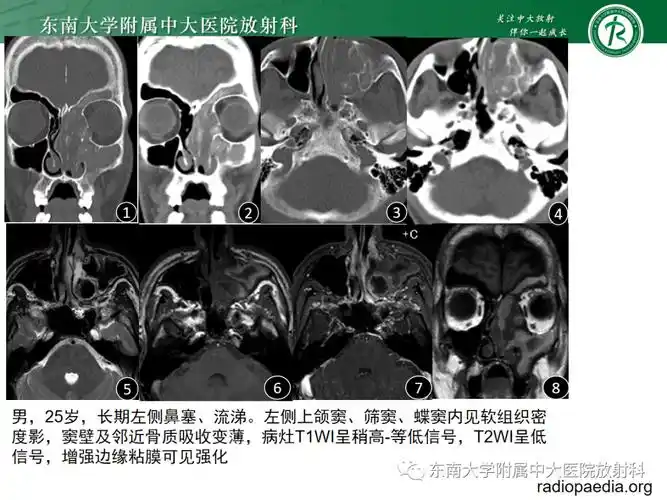

真菌性鼻窦炎影像学诊断